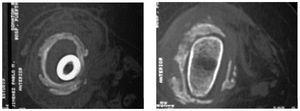

Figs. 3 y 4.—Intensa reacción perióstica y ensanchamiento metafisario a nivel distal de fémur. / Figs. 3 and 4.—Intense periosteal reaction and metaphyseal widening at the distal level of the femur.

Ingresó en nuestro servicio para estudio de tumoración indolora en cara lateral del muslo izquierdo de una semana de evolución, con importante inflamación de todo el miembro inferior izquierdo y aumento de temperatura del mismo, sin que existiese ningún antecedente traumático evidente ni signos de infección en la analítica general. De inicio fue descartada patología de origen vascular mediante la realización de Eco-doppler que mostró la presencia de una masa de partes blandas con ligera compresión del paquete vascular que provocaba el edema distal. Se solicitaron estudios radiológicos que mostraron una epifisiolisis distal de fémur tipo I de Salter acompañada de una importante tumoración con una intensa reacción perióstica alrededor que envolvía desde la metáfisis inferior al tercio medio de la diáfisis (figs. 1 y 2). Planteamos el diagnóstico diferencial entre miositis osificante, hematoma calcificado y tumoración de partes blandas, por lo que se solicitan nuevas pruebas complementarias. La gammagrafía ósea informó de una intensa y patológica vascularización y fijación del radio-trazador a nivel de mitad distal del fémur izquierdo, que podría ser compatible con tumor óseo (¿osteosarcoma?) o displasia fibrosa. Por su parte, el estudio con RNM describía una tumoración compuesta por zonas de proliferación, escasas zonas de calcificación, engrosamiento metafisario y del periostio. Se realizó TAC óseo que mostró una intensa reacción perióstica y ensanchamiento metafisario a nivel distal de fémur (figs. 3 Y 4). Finalmente se procedió a la realización de biopsia con aguja percutánea, cuyo examen histológico reveló largas áreas de sangre antigua y exuberante tejido conectivo fibroso, áreas de calcificación distrófica interpuestas entre el tejido, sin evidencia de formación de callo o degeneración maligna.